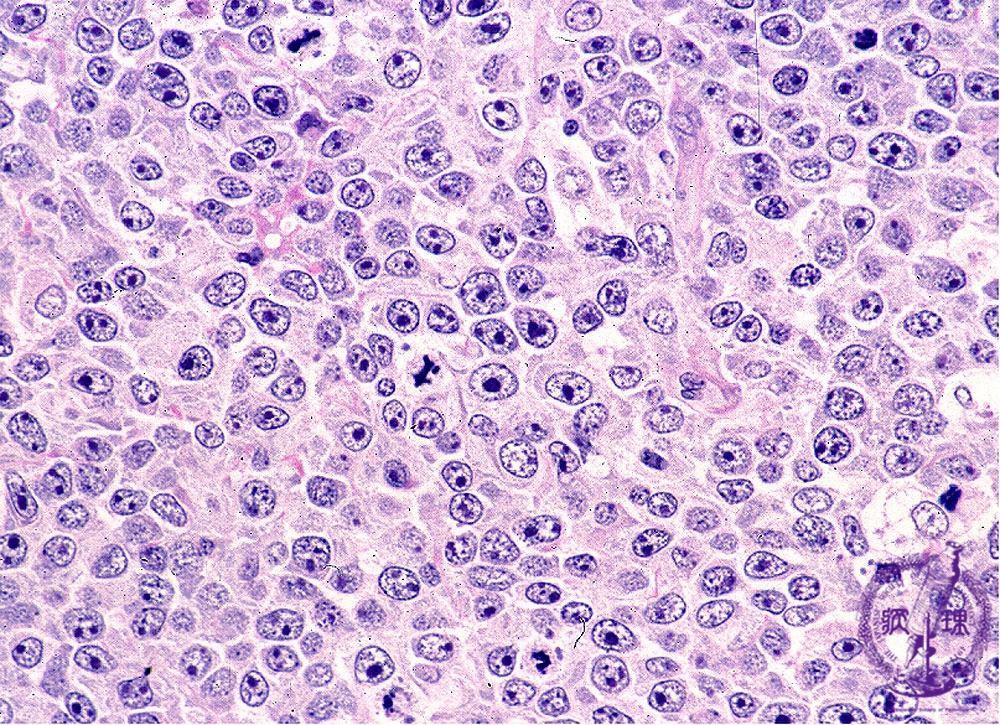

- ★(6)Diffuse large B-cell lymphoma

Microscopic image (H&E high power view): The tumor cell nuclei are more than double (arrows) in size than those of mature lymphocytes (arrow head) and contain multiple nucleoli. Cytoplasm is relatively scant and mitotic figures are numerous.